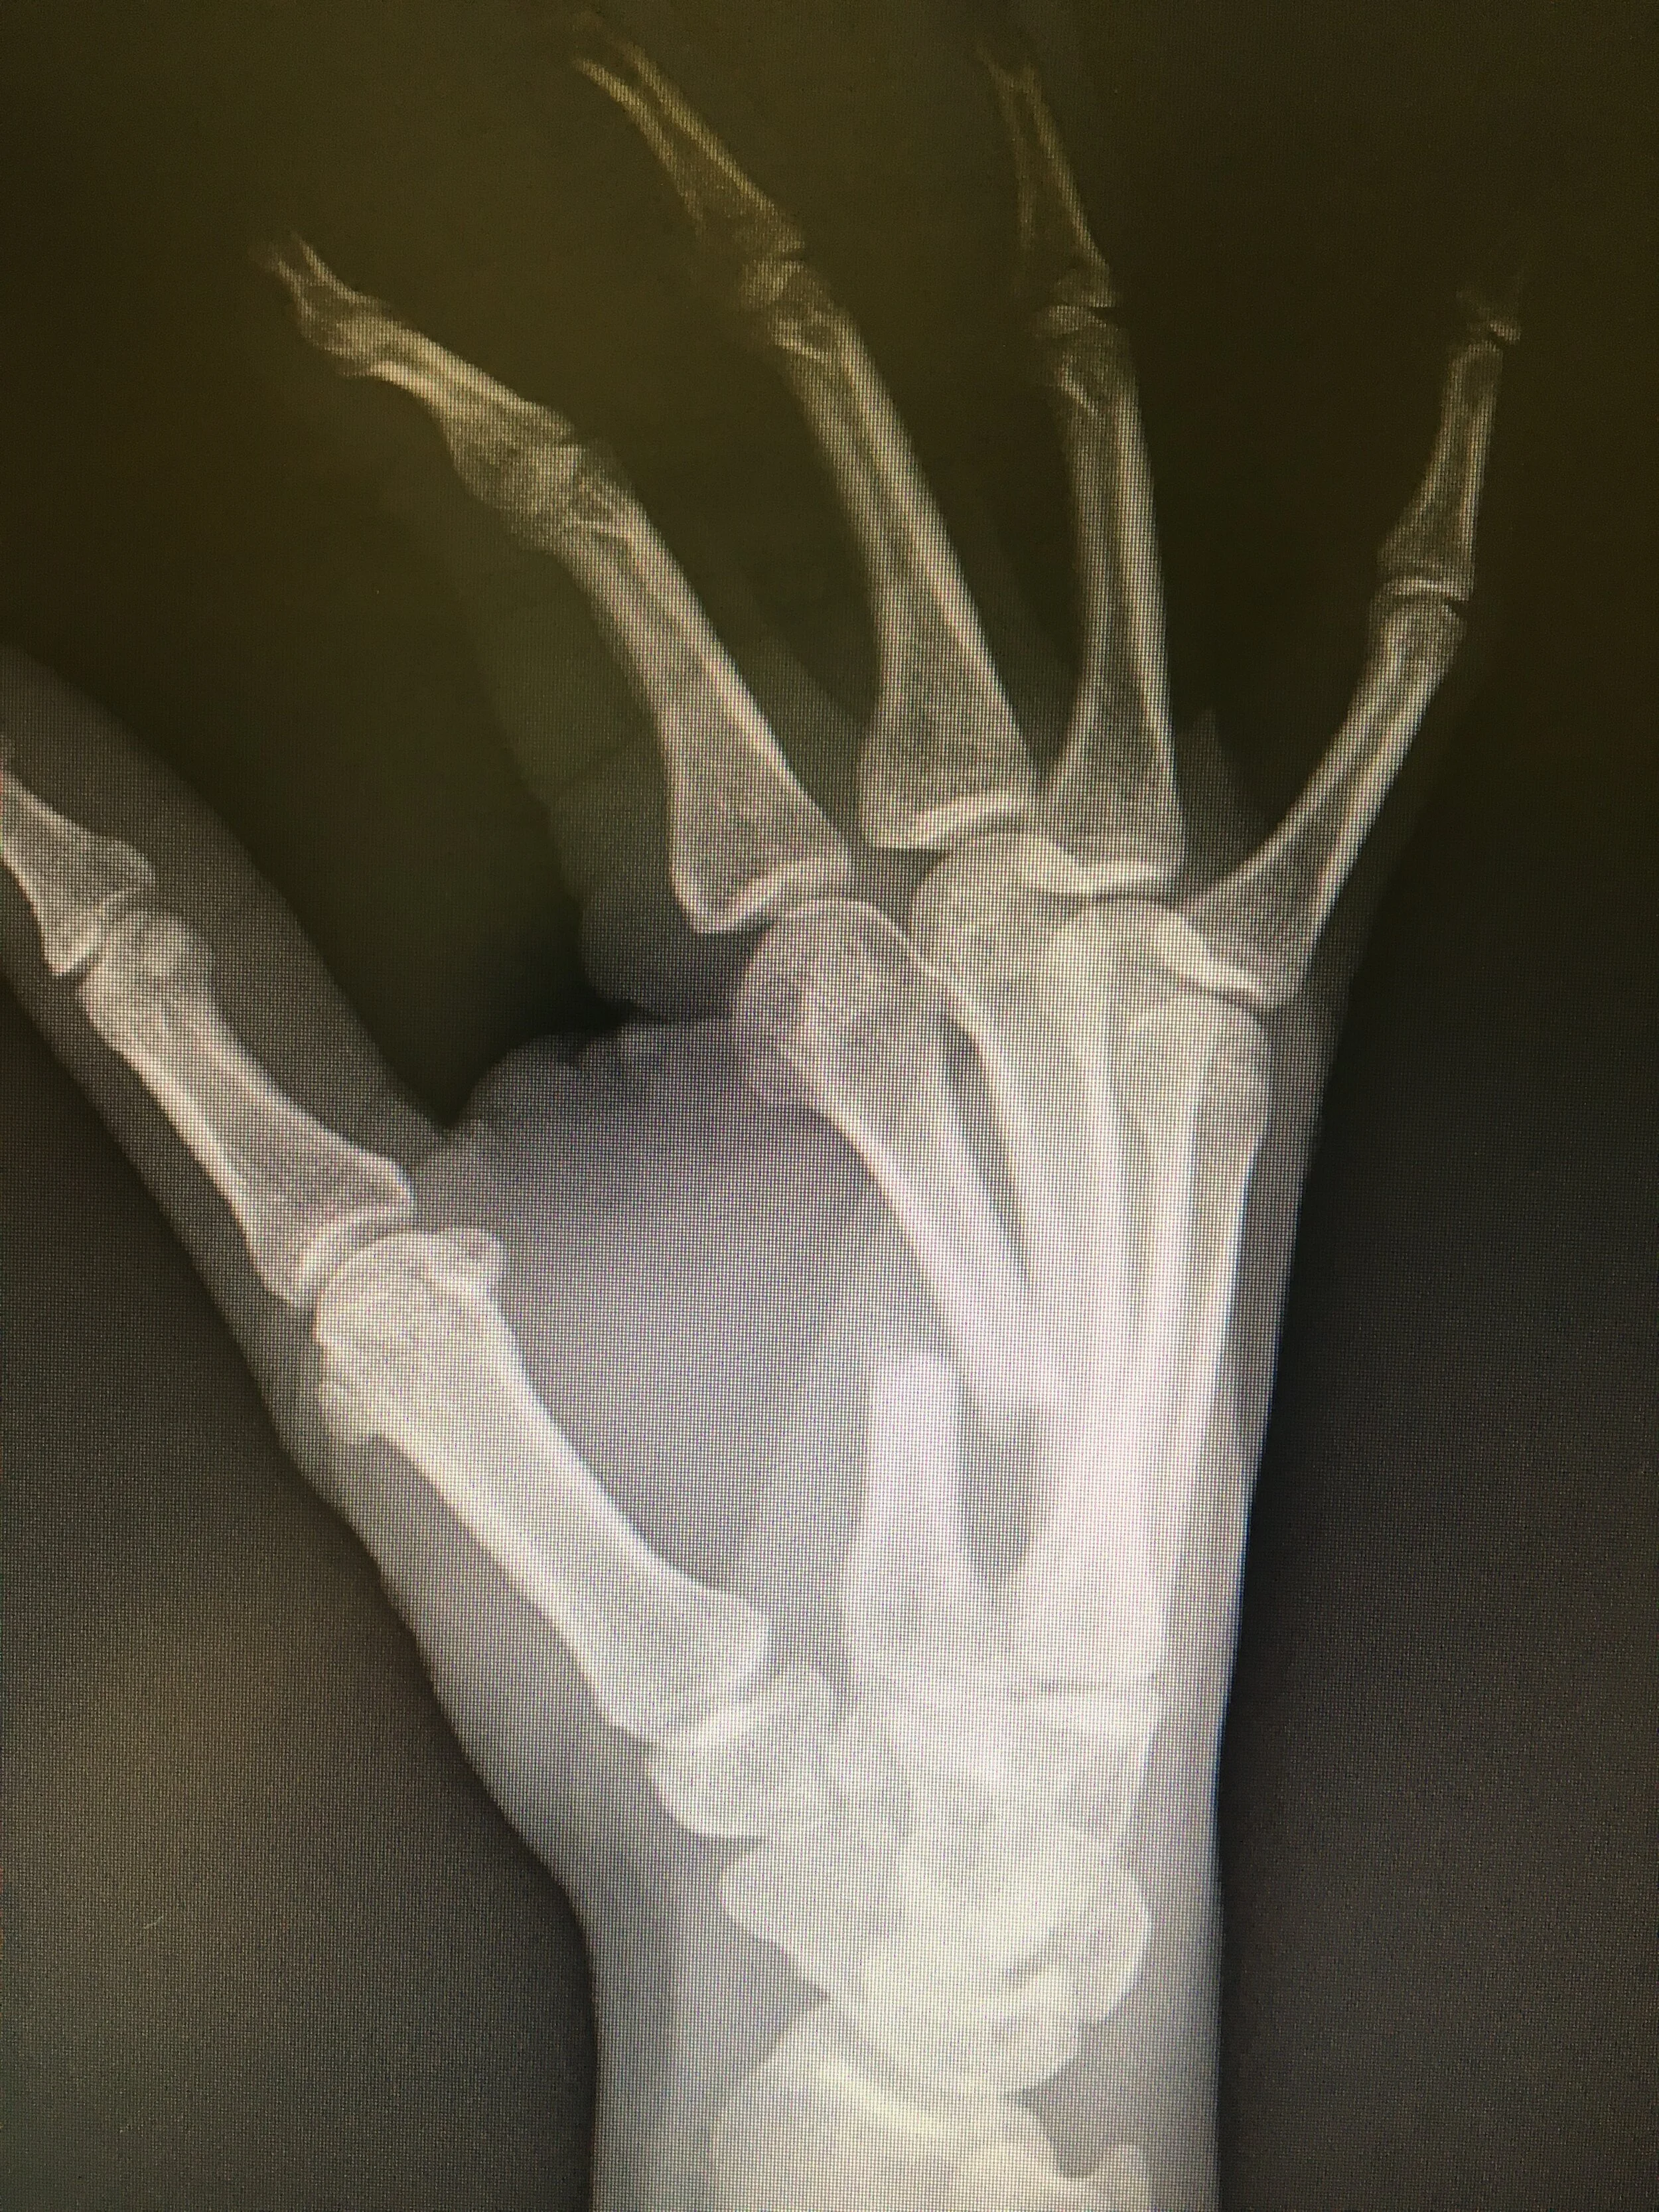

Orthopaedic Surgery

IMG_0038.JPG